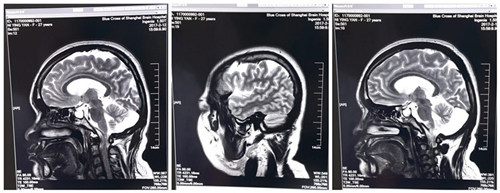

术前:双侧侧脑室旁、半卵圆中心及额顶叶多发灶

不出意料,手术非常成功,术后,这名患者(倪红,27岁)的癫痫病情控制良好,目前已经出院。